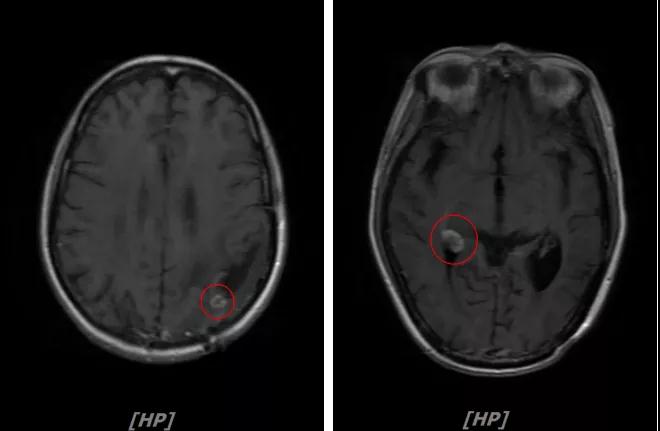

头颅增强MR:左侧顶枕叶见片状T1WI低信号、T2WI高信号影,增强后病灶边缘见局部斑片状强化改变,邻近脑膜轻度强化改变;右侧脑室三角区内侧见大小约8x14mm的结节影,T1WI低信号、T2WI等高信号,增强明显强化,灶周水肿明显;两侧脑室旁见片状异常信号,T1WI低信号,T2WI高信号,增强未见明显强化,余脑室、脑池、脑沟大小形态可,中线结构居中无移位

左顶叶脑转移瘤术后放疗后,左顶叶术区边缘强化灶;考虑肿瘤复发

右侧脑室三角区内侧转移瘤

两侧脑室旁云絮状异常信号,考虑放疗后改变

患者一线治疗的PFS为37个月。2017年1月,患者二线治疗为在原“拉帕替尼+阿那曲唑”基础上,加曲妥珠单抗治疗。患者头痛症状有所改善,病灶缩小,继续定期复查。